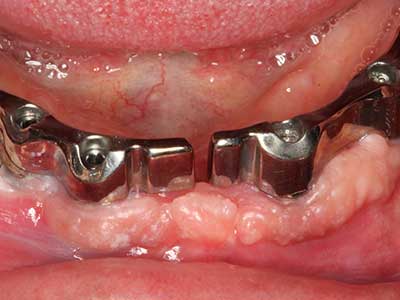

Abb. 13: Bei diesem 52-jährigen Patienten ist bei 4 mm UK-Restknochenbreite während des Bone Splittings auf eine ausreichende Wasserkühlung zu achten.

Abb. 14: Einbringung von vier konischen RSX-Implantaten (Bego Implant Systems, Bremen).

Abb. 15: Die röntgenologische Ein-Jahres-Kontrolle zeigt stabile Verhältnisse des Knochenniveaus.

Abb. 16: Auch intraoral stabile Verhältnisse mit Einbettung der Implantate in keratinisierter Gingiva.